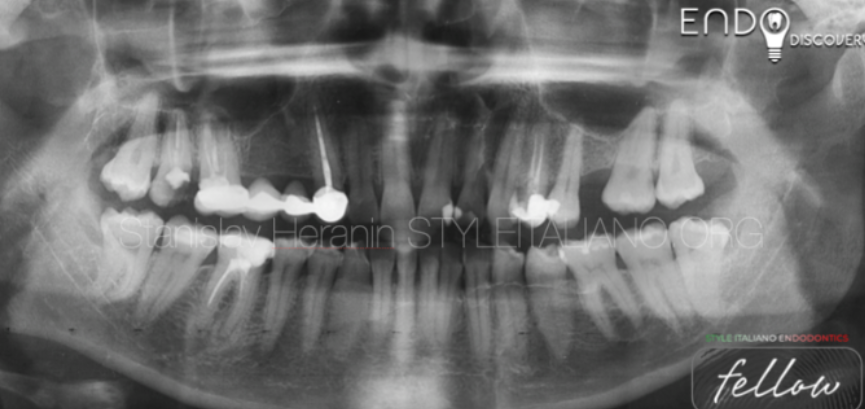

然而大面积牙体缺损边缘的龈下位置增加了瓷嵌体修复的操作难度,并对修复体的使用寿命和牙周健康产生不利影响.龈壁提升技术通过充填材料重新堆塑,使邻面边缘升至龈上,为之后的上障,取模,粘接等操作提供有利条件.换言之龈壁提升技术就是嵌体修复的保障。

滑动查看龈壁提升前后照片

案例实操